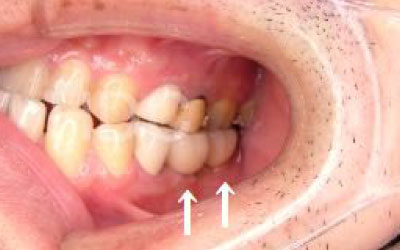

少しの位置ズレであれば、噛み合わせを調整したり、小さな詰め物で対処することができます。

しかし抜けてから数年が経ち、大きく傾いてしまった歯の場合は、歯並びを矯正するか、歯を大きく削ってかぶせ物をする必要があります。